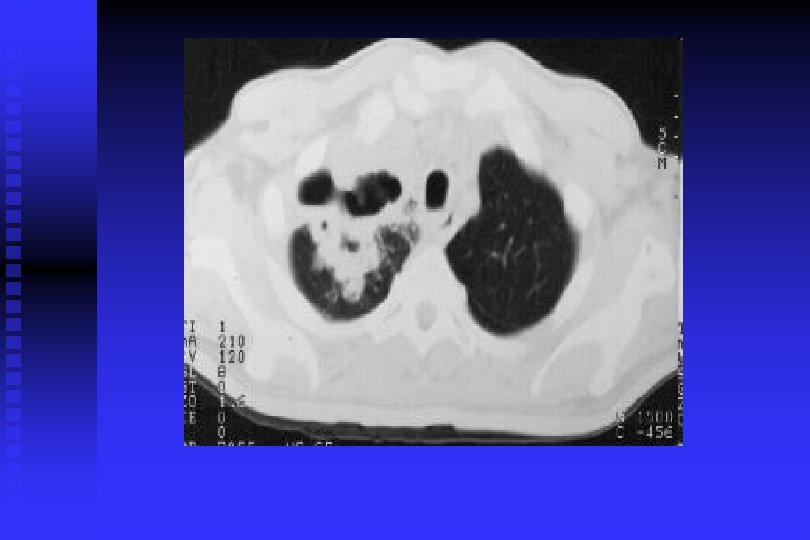

Cancer Pulmonar

DIAGNOSTICO DE CANCER PULMONAR RADIOGRAFIA DE TORAX: Permite descubrir CP en asintomáticos en 67 -82% y de estos el 24% tiene citología de esputo anormal. TOMOGRAFIA DE TORAX: Sensibilidad del 85% para CP y una especificidad del 95%. Per– mite descartar causas benignas de nódulos pulmonares con uni – dades Hounsfield >175= benigno; adenopatías <1 cm= benignos; 1 -2 cm= Indeterminado, >2 cm= positivo. Permite conocer actividad metastásica, y para estadificación (S= 73% y E= 80%).